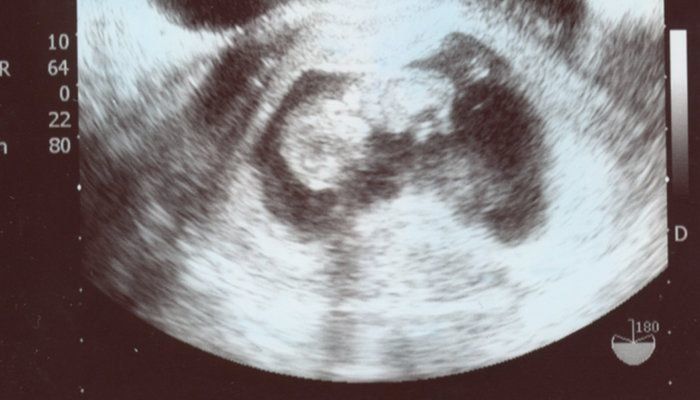

こぢんまり子さんの妊娠9週目のエコー写真 おなかの中ですくすく成長する赤ちゃん

右側が頭、左側が体です。頭と体がなんとなく分かれて、体の下側に小さな手と足がついています。「頑張って成長してくれているな」とうれしくなりました。2番目の子を連れて産院に行ったのですが、診察室には入らず、前室で看護師さんとおもちゃで遊びながら大人しく待っていてくれました。